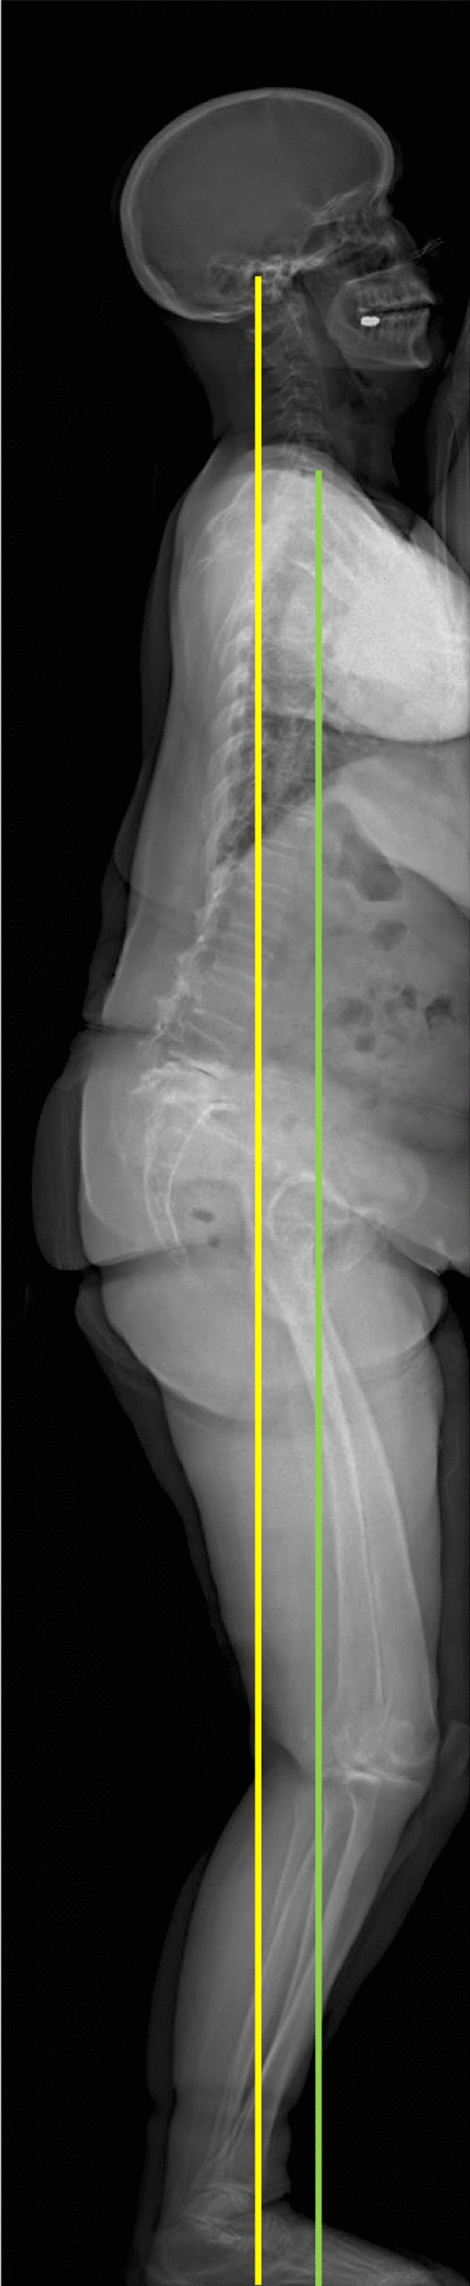

Background: Knee flexion contracture (KFC) progression after total knee arthroplasty (TKA) can significantly affect functional outcomes through disruption of the biomechanical knee-hip-spine kinetic chain. This study was conducted to investigate whether preoperative global sagittal alignment parameters, particularly the center of the acoustic meatus-sagittal vertical axis (CAM-SVA), could predict short-term KFC progression after TKA.

Methods: A retrospective case-control study was performed on 760 consecutive TKA cases, with 347 knees meeting inclusion criteria. KFC progression was defined as > 5° increase in knee flexion angle between immediate postoperative and final follow-up radiographs. Demographic factors and radiographic parameters were analyzed using univariate and multivariate logistic regressions. Patient-reported outcomes were assessed using the American Knee Society Score (AKSS) and the Western Ontario and McMaster Universities Osteoarthritis Index (WOMAC). Potential sources of bias were addressed through standardized measurement protocols and inter-observer reliability testing.

Results: KFC progression was observed in 39 knees (11.2%), with mean progression of 8.0 ± 3.8° over 23.5 ± 13.1 months. Multivariate analysis revealed that CAM-SVA and age were independently associated with KFC progression (odds ratio: 1.02 [95% CI 1.01-1.04], p < 0.05; and 1.09 [95% CI 1.02-1.17], p < 0.01, respectively). At 12 months, the KFC progression group demonstrated significantly lower AKSS scores and higher WOMAC scores (p < 0.05) as compared to the nonprogression group.

Conclusions: CAM-SVA and advanced age were identified as independent predictors of KFC progression following TKA, supporting the hypothesis that global sagittal malalignment contributes to compensatory knee flexion through biomechanical interdependence of the knee-hip-spine kinetic chain. Assessment of preoperative global sagittal alignment may help identify patients at risk for KFC progression and inform individualized treatment strategies.